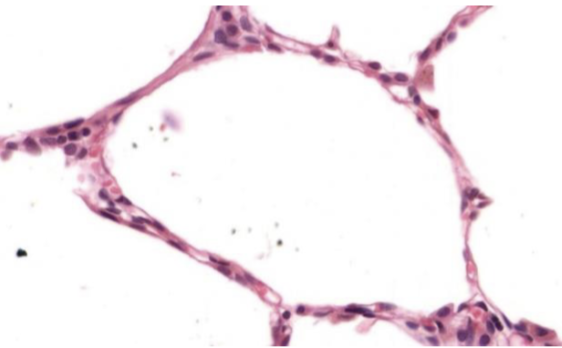

Indique órgano o sistema que posee este epitelio

alveolo

Forma de sus células

plano

Número de estratos

simple